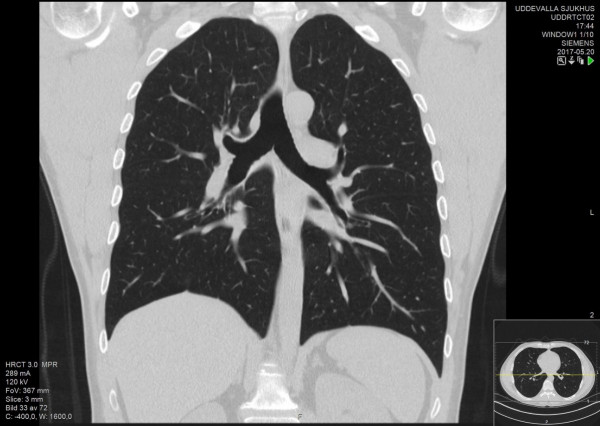

رصد أطباء ألمان علامات خطيرة لدى مصابي فيروس كورونا المستجد في البلاد، تتمثل بظهور غيوم غريبة في الرئة ، أثناء القيام بالتجارب الاستكشافية الأولى لرصد سلوك فيروس كورونا المسبب لمرض "كوفيد 19"، والتي استمرت لأسابيع.

وبحسب ما نقلته وكالة "سبوتنيك"عن وسائل إعلام محلية ، فقد رصد العلماء الألمان غيوما ساطعة غير عادية يسببها فيروس كورونا المستجد على حافة رئتي المصاب وتسببت هذه الظاهرة بارتباك العلماء وحيرتهم، حيث ما زال خبراء الفيروسات لا يستطيعون فهم طبيعة جينوم الفيروس.

وأشار الخبراء إلى أن الفيروس بمجرد وصوله إلى الجهاز التنفسي السفلي يخترق خلايا الرئة، فيتسبب بالتهاب شديد بسبب محاربته من قبل جهاز المناعة، ولكن بشكل مختلف وغريب تماما عما ألفه الأطباء في الالتهابات الرئوية العادية.

وقال رئيس قسم أمراض الرئة في مستشفى دوناوستوف الألماني، ميشائيل بفايفر، إنه من "المحتمل جدًا أن تتجمع كمية أقل بكثير من السوائل في الرئتين في المرحلة الأولى من فيروس كورونا المستجد، مقارنةً بالالتهاب الرئوي الكلاسيكي".